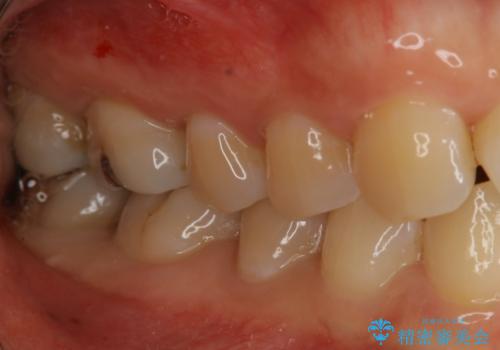

奥歯を綺麗にしたい

- 右下6・7番の咬合面に詰められた保険材料が劣化していたので、審美性・切削量を考慮しセラミックインレー治療を選択しました。

劣化した保険材料・虫歯を全て除去した上で形成しています。